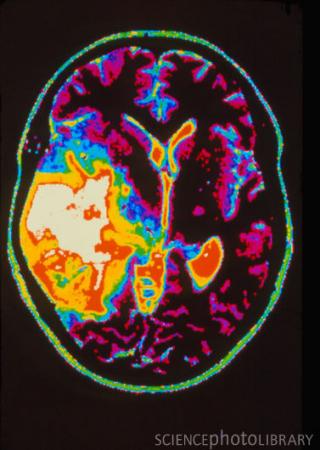

脑癌MRI扫描(图)

少突胶质细胞瘤(Oligodendrogliomas)是从少突胶质细胞发生的肿瘤。多发生在大脑的浅部,生长缓慢,界限不清,是由富于圆形和具有蜂窝状特征(honeycomb architecture)的细胞所构成的神经胶质瘤。这种疾病是常见的恶性脑瘤之一,占成人中所有脑肿瘤的约20%。多年来医学界多年来一直在寻找少突胶质细胞瘤的主要致病基因变异,但是尽管确定了相关变异发生在人类1号和19号染色体,依然未能发现其中的关键基因变异。